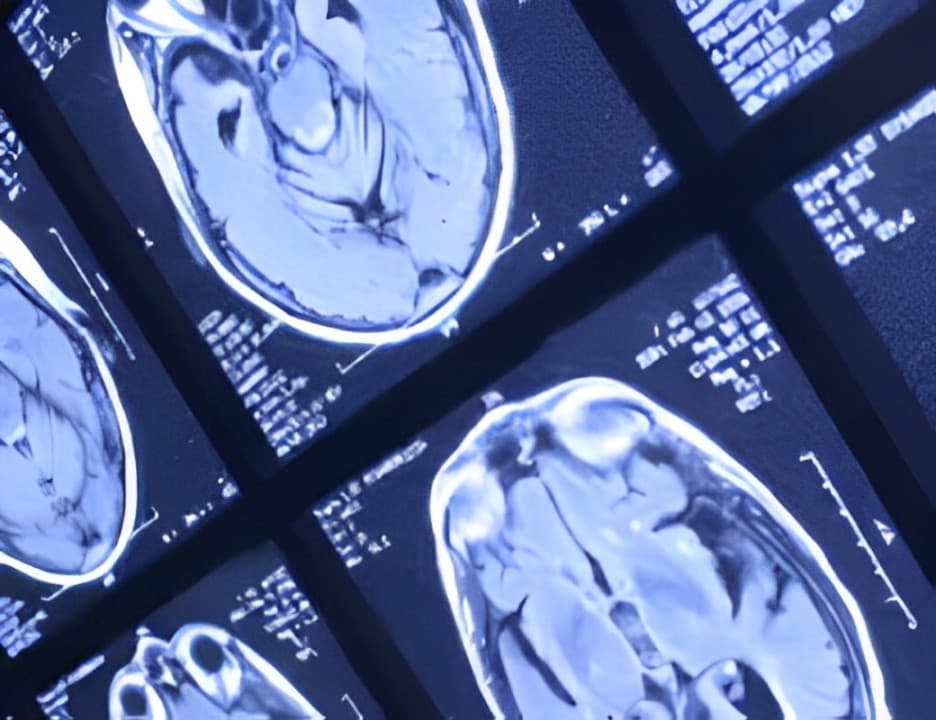

Glioblastoma (GBM) impacts nearly 13,000 individuals each year in the United States and approximately 300,000 worldwide, with a staggering mortality rate of 94%. For patients with GBM, existing standard treatments typically lead to a life expectancy of less than 15 months. One of the significant challenges in developing new drugs for GBM is the necessity for these therapies to effectively cross the blood-brain barrier (BBB) and to overcome the natural and adaptive resistance that GBM cells exhibit against temozolomide, the current first-line treatment.